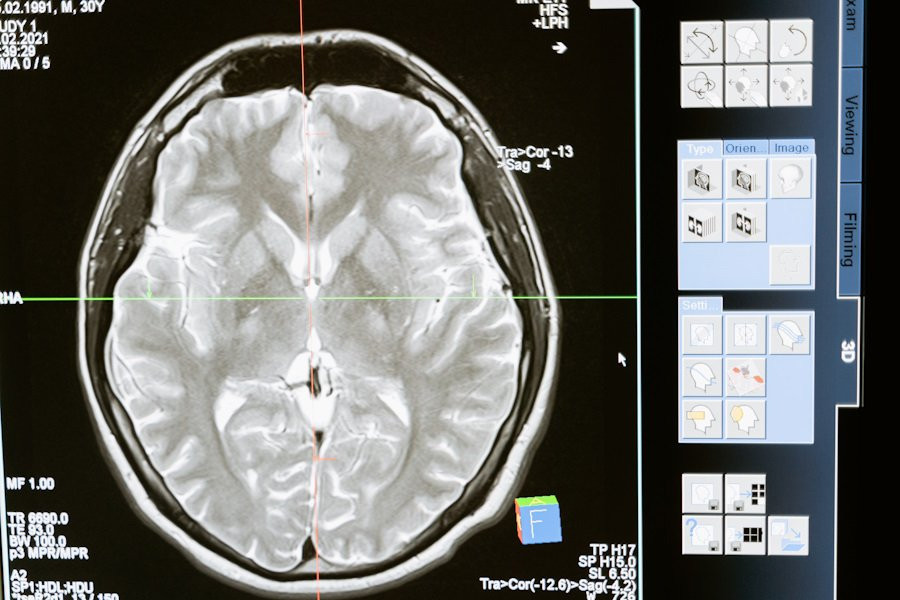

Ученые из EMBL и Heidelberg University сделали реальностью то, что раньше казалось фантастикой: создана технология, способная следить за клетками глиобластомы, одной из самых агрессивных форм рака мозга, по «супершоссе» нервных волокон — мозолистому телу, которое соединяет два полушария мозга. Этот «смотритель» — передовая микроскопия с элементами искусственного интеллекта, позволяющая заглянуть в самые глубокие слои мозга и отслеживать раковые клетки в реальном времени.

Согласно порталу Nature Communications, исследователи добились улучшения технологии глубокотканевой микроскопии. С помощью ИИ они смогли устранить помехи в изображениях и четко различить структуры, такие как миелинизированные волокна и кровеносные сосуды, что крайне важно для понимания поведения опухолевых клеток в контексте их окружающей среды. Теперь ученые могут наблюдать за тем, как клетки глиобластомы проникают в плотные нервные волокна и распространяются по мозгу.